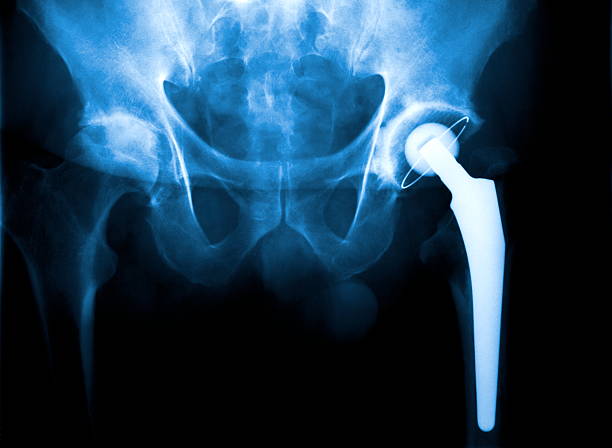

고관절 충돌 증후군은 엉덩이 통증의 주요한 원인 중 하나입니다. 이 질환은 골반 뼈와 대퇴골 사이에서 발생하는 충돌에 의해 2 관절 사이의 연골이 손상되는 질환입니다. 고관절의 구조적인 문제나 잘못된 자세, 과도한 스트레칭 등으로 발생할 수 있습니다.

관절염

엉덩이 관절의 염증이나 변형으로 인해 엉덩이 통증이 발생할 수 있습니다. 나이가 들어가면서 관절염이 악화되어 엉덩이 통증이 생기는 경우가 많습니다. 이러한 경우에는 전문의의 치료와 적절한 관리가 필요합니다.